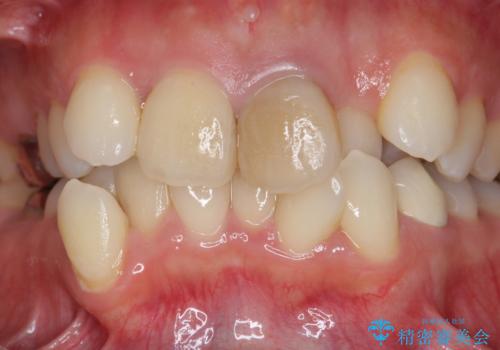

- 26.4万円(ジルコニアクラウン×2・仮歯×2)費用は治療当時の料金となります

清掃を難しくしている歯を抜去することで虫歯の再発を防ぐような治療方針としました。